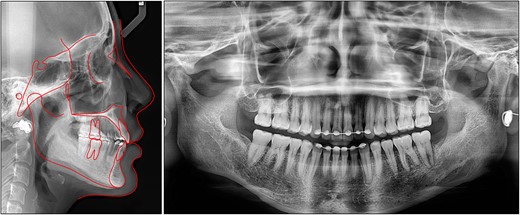

On a lateral cephalometric evaluation, the patient had a skeletal class I relationship (point A-nasion-point B angle, 4.0°) with a hyperdivergent facial pattern (Frankfort mandibular angle, 32.5°) (Table 1). The panoramic radiograph showed the presence of all teeth including the third molars (Fig. 2). The patient was diagnosed with an iatrogenic open bite and class II malocclusion on a skeletal class I relationship.